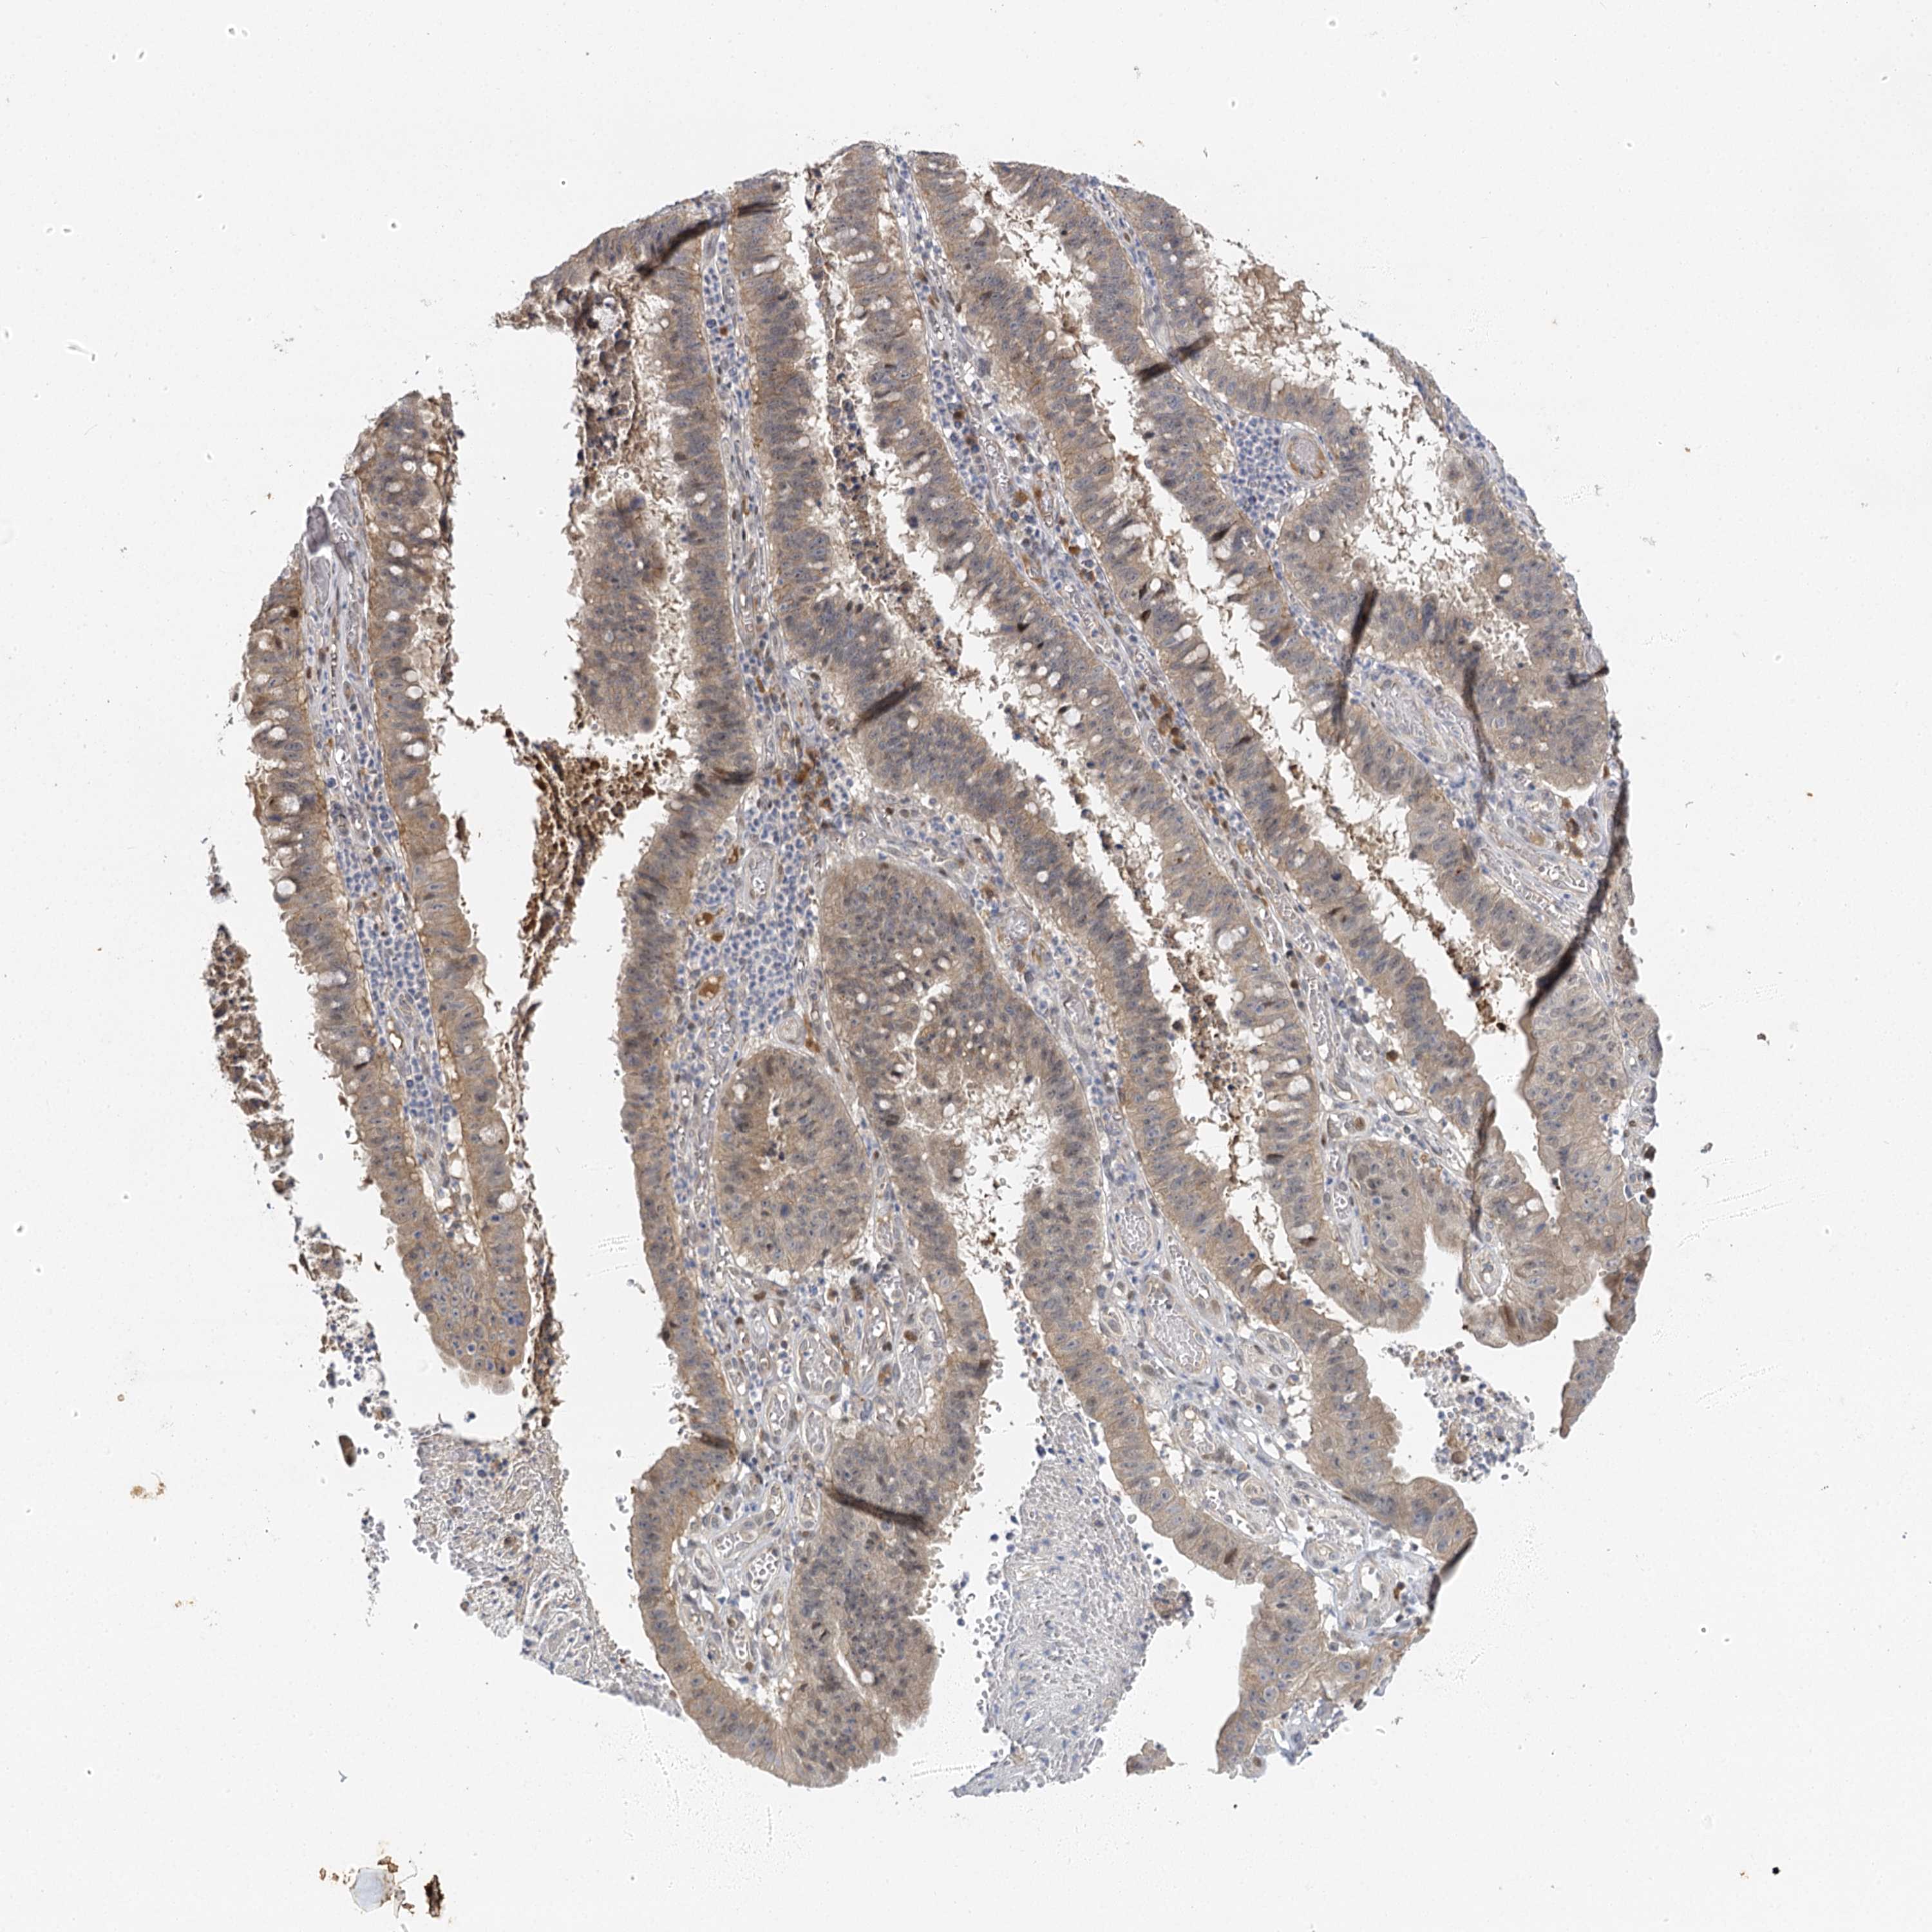

STOMACH CANCER - Protein expressioni

A mouse-over function shows sample information and annotation data. Click on an image to view it in a full screen mode. Samples can be filtered based on level of antibody staining by selecting one or several of the following categories: high, medium, low and not detected. The assay and annotation is described here.

Note that samples used for immunohistochemistry by the Human Protein Atlas do not correspond to samples in the TCGA dataset.

Antibody stainingi

Antibody staining in the annotated cell types in the current human tissue is reported as not detected, low, medium, or high, based on conventional immunohistochemistry profiling in selected tissues. This score is based on the combination of the staining intensity and fraction of stained cells.

Each image is clickable and will lead to virtual microscopy that enables deeper exploration of all samples and also displays staining intensity scores, fraction scores and subcellular localization as well as patient and tissue information for each sample.

Antibody HPA013162

Antibody HPA036652

Antibody CAB032830

Staining

High

Medium

Low

Not detected

Intensity

Strong

Moderate

Weak

Negative

Quantity

>75%

75%-25%

<25%

None

Location

Nuclear

Cytoplasmic/membranous

Cytoplasmic/membranous,nuclear

Adenocarcinoma, NOS

Adenocarcinoma, High grade